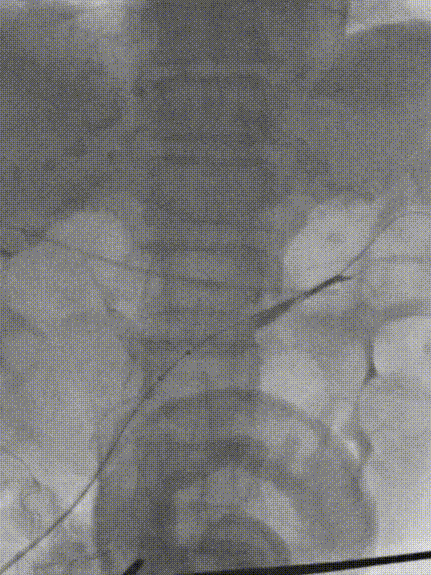

2. 吸栓后造影,明确门静脉残端。

3. 经颈静脉置入10F导管鞘,下腔静脉置入大球囊在预定穿刺位置。

4. 经肠系膜静脉入路置入可调弯导管和空芯穿刺套件,调整方向后穿刺。